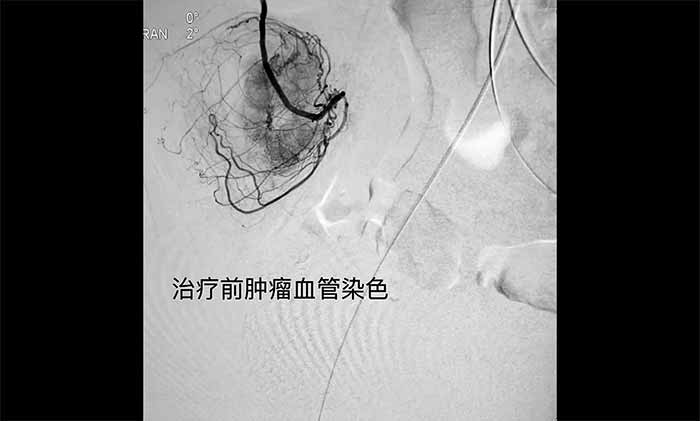

▲ 手术前肿瘤血管染色

术中,王永利教授联合侯安继主任、黄运星医生,首先根据造影图像,确认导管在肿瘤供血动脉分支内。经微导管灌注化疗药物,并对血管进行栓塞。完成后经微导管造影,见肿瘤血管供血和染色已明显减少。术后,便血已基本得到控制。